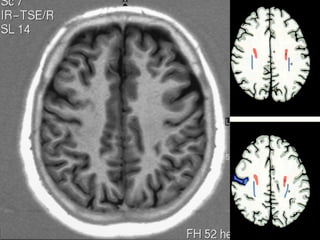

CENTRO SEMIOVAL/COROA RADIATA

MESENCÉFALO COLÍCULOS SUPERIORES COLÍCULOS INFERIORES

• TETO MESENCEFÁLICO(LÂMINA QUADRIGEMINAL) • PEDÚNCULOS CEREBELARES SUPERIORES E INFERIORES • IV VENTRÍCULO • CEREBELO - HEMISFÉRIOS

MESENCÉFALO SUBSTÂNCIA CINZA PERI- AQUEDUTAL SUBSTÂNCIA NIGRA/ NÚCLEOS RUBRO